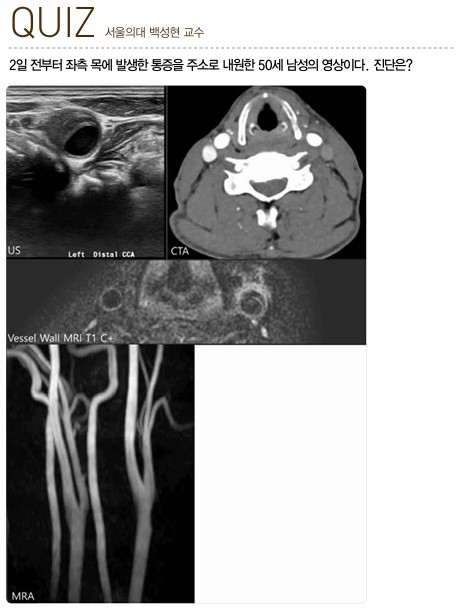

퀴즈